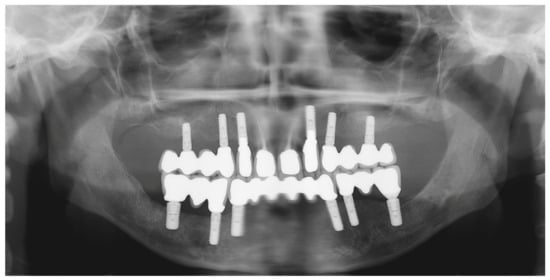

Figure 29.

Panoramic radiograph showing the dental implants in place.